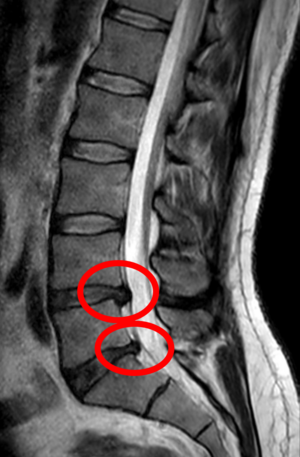

- التصوير بالرنين المغناطيسي هي الدراسة المعيارية الذهبية لتأكيد الاشتباه في انزلاق غضروفي. مع دقة تشخيصية تبلغ 97%، فهي الدراسة الأكثر حساسية لتصور الانزلاق الغضروفي بسبب قدرتها الكبيرة على تصور الأنسجة الرخوة. كما يتمتع التصوير بالرنين المغناطيسي بموثوقية أعلى بين المراقبين مقارنة بوسائل التصوير الأخرى. ويشير إلى انزلاق غضروفي عندما يظهر إشارة متزايدة مرجحة بـ T2 عند المنطقة الخلفية التي تغطي 10% من القرص. وقد أظهرت أمراض الانزلاق الغضروفي ارتباطًا بتغيرات النوع 1 من مقياس موديك. عند تقييم اعتلالات الجذور العصبية القطنية بعد الجراحة، فإن التوصية هي إجراء التصوير بالرنين المغناطيسي مع التباين ما لم يكن هناك موانع أخرى. يعد التصوير بالرنين المغناطيسي أكثر فعالية من التصوير المقطعي المحوسب في التمييز بين الأسباب الالتهابية أو الخبيثة للانزلاق الغضروفي. يُشار إليه في وقت مبكر نسبيًا في مسار التقييم (<8 أسابيع) عندما يظهر المريض مؤشرات نسبية مثل الألم الشديد والعجز الحركي العصبي ومتلازمة ذيل الفرس. التصوير الموتر الانتشاري هو نوع من تسلسل التصوير بالرنين المغناطيسي المستخدم للكشف عن التغيرات الدقيقة في جذر العصب. قد يكون مفيدًا في فهم التغييرات التي تحدث بعد أن يضغط القرص القطني المنفتق على جذر العصب، وقد يساعد في التمييز بين المرضى الذين يحتاجون إلى تدخل جراحي. في المرضى الذين لديهم شكوك عالية في اعتلال الجذور العصبية بسبب الانزلاق الغضروفي القطني، ومع ذلك فإن التصوير بالرنين المغناطيسي غامض أو سلبي، يوصى بدراسات التوصيل العصبي.[44] توفر الصور المرجحة الناتجة عن التصوير بالرنين المغناطيسي (T2) تصور واضح لمادة القرص البارز في القناة الشوكية.